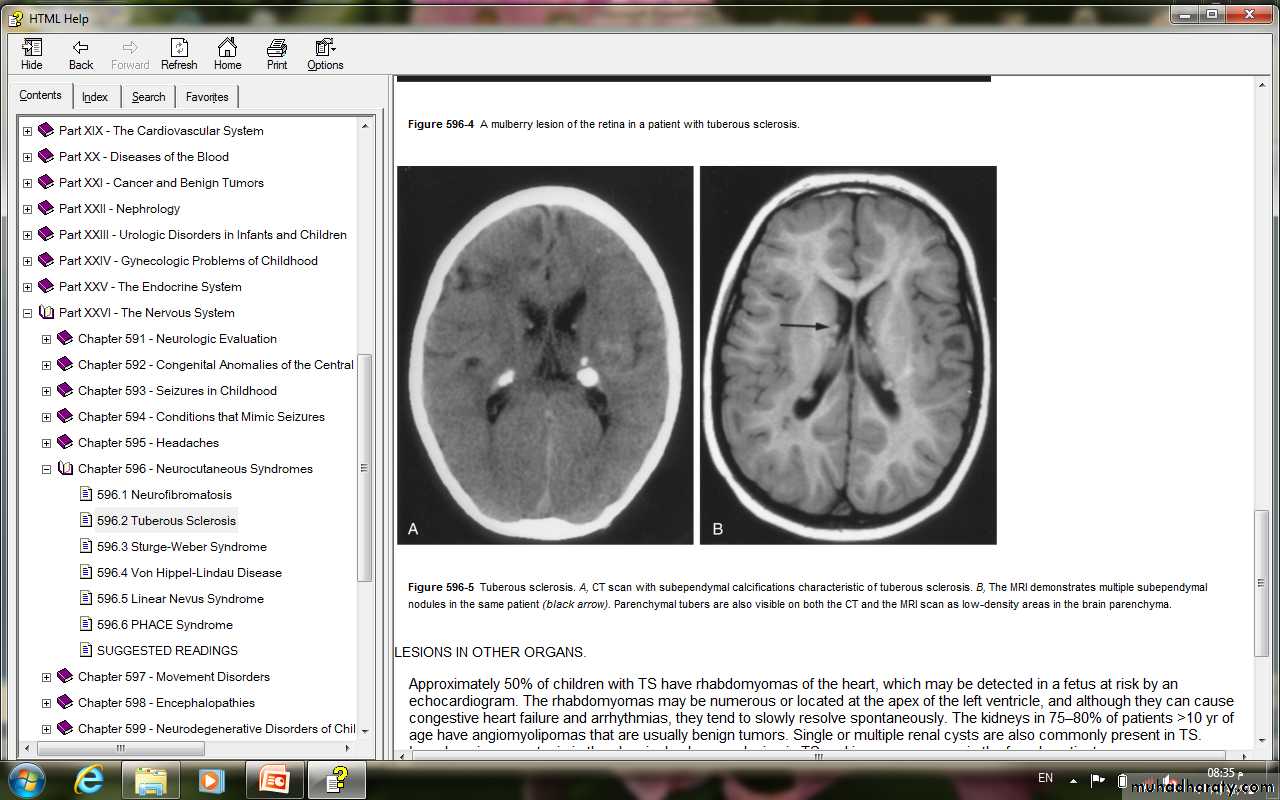

• Retinal lesions consist of two types: mulberry tumors that arise from the nerve head or round and hamartoma• The characteristic brain lesion is a cortical tuber.

• Tubers in the region of the foramen of Monro may cause obstruction of CSF flow and hydrocephalus.• MRI is useful for identification of the lesions.